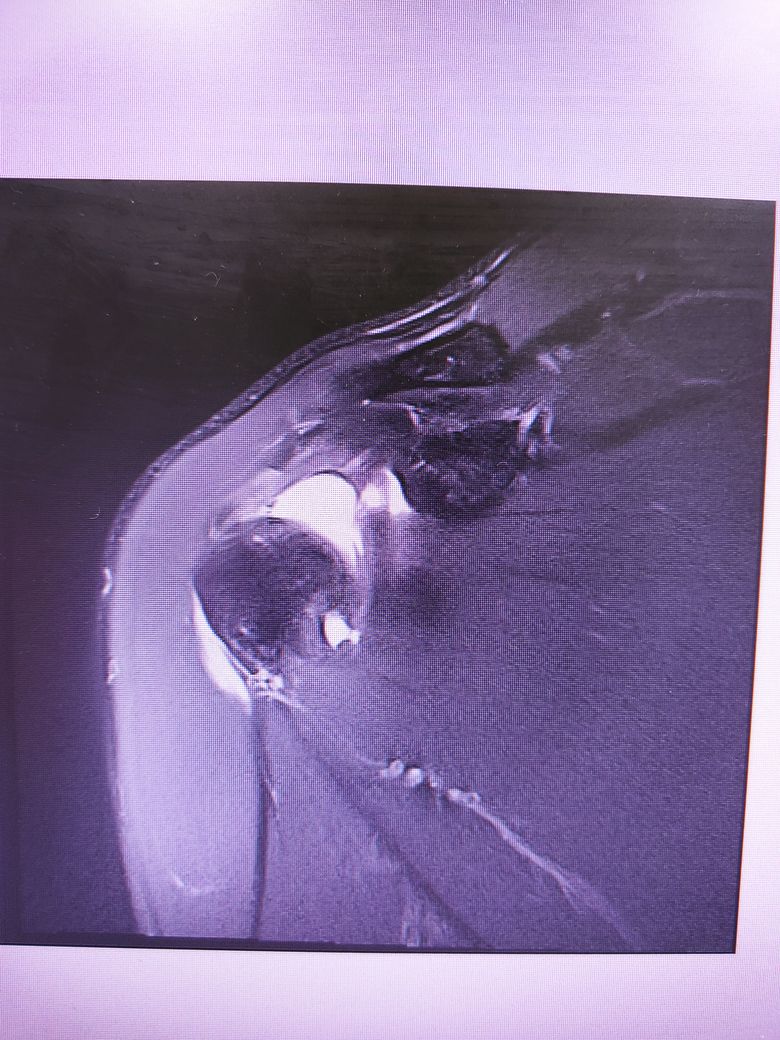

팔이 잡아당겨지는 사고 이후 통증이 지속되어

조영제 투입 후 mri 촬영을 하였습니다.

진단명은 상부관절와순파열(슬랩)이며

헬스와 같은 운동을 계속 하려면 수술이 필요하다 하였습니다.

슬랩이 맞나요? 맞다면 파열 진행 정도는 어느정도인지..

궁금합니다..최대한 사진 많이 올립니다 감사합니다..